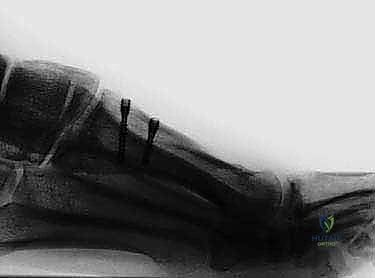

يتم إجراء القطع العظمي بشكل مائل، بدءاً من السطح الأخمصي القريب (Plantar-proximal) إلى السطح الظهري البعيد (Dorsal-distal). هذا الاتجاه المائل للقطع يوفر استقراراً ميكانيكياً هائلاً ضد قوى الإزاحة التي تحدث أثناء تحمل الوزن والمشي.

الخطوة الرابعة: إعادة التوجيه والتثبيت الداخلي

بعد قص العظم، يتم تحريك الجزء البعيد (الذي يحمل المفصل والإصبع) نحو الخارج لتصحيح التشوه وتضييق المسافة بين الأمشاط. بمجرد الوصول للوضع المثالي، يتم تثبيت العظمين معاً بقوة باستخدام برغيين أو ثلاثة من التيتانيوم الطبي عالي الجودة. هذه البراغي تدفن داخل العظم ولا تحتاج للإزالة لاحقاً.

بعد التأكد من استقرار العظم ووضعه المثالي (غالباً باستخدام جهاز أشعة سينية داخل غرف العمليات Fluoroscopy)، يتم إزالة النتوء العظمي المتبقي. أخيراً، تُغلق الكبسولة المفصلية والجلد بخياطة تجميلية دقيقة لتقليل الندبات، وتوضع ضمادات ضاغطة خاصة.